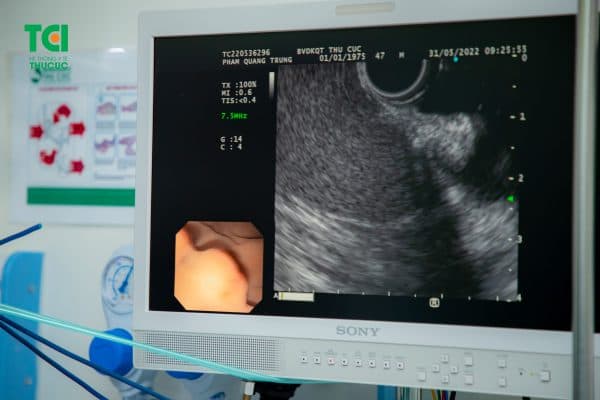

Hình ảnh minh họa của nội soi đại trực tràng.

Hình ảnh nội soi MCU được phóng đại gấp 100 lần, phát hiện mọi tổn thương.

Siêu âm nội soi giúp chẩn đoán về mức độ xâm lấn của tổn thương.